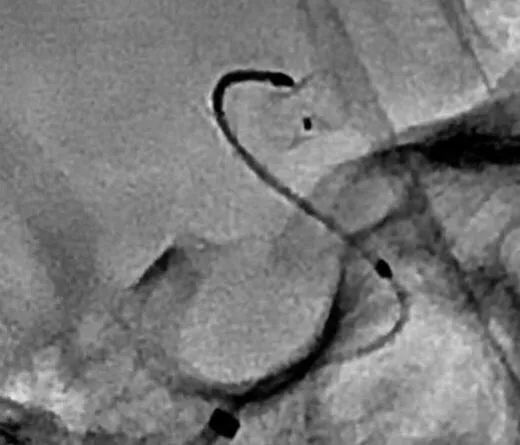

CASE 2 AN

-责任动脉直径约2mm,使用新型血流导向装置FRED Jr. 实现血流重构

-FRED Jr. 为双层支架,远端无导丝